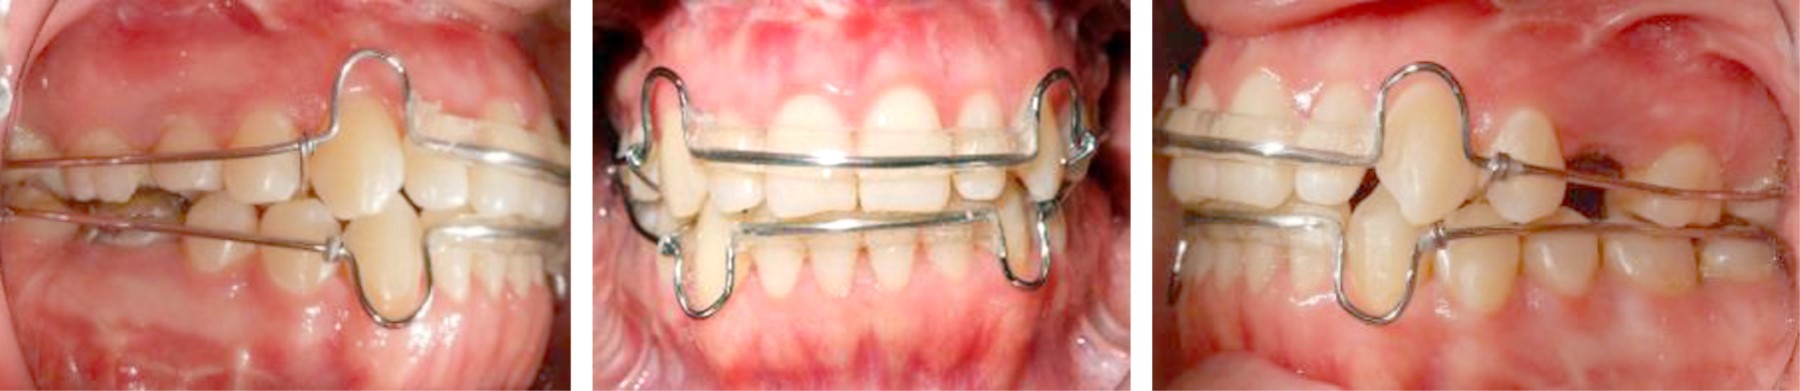

After 12 months the case was reevaluated with the taking of study and work models, lateral and posteroanterior radiography, and orthopantomography, and together with the Surgery Department of DEPeI, UNAM, the orthognathic surgery was programmed (Figure 8).

Presurgical 0.019" × 0.025" stainless steel surgical arches with crimpable hooks were placed. The surgical procedure consisted of bilateral branch sagittal for correction of laterognathia, mandibular retroposition, and maxillary impaction for correction of vertical excess. Eight 8 mm fixation screws were used, three on each side. Seven days after surgery, intermaxillary elastics were placed to achieve adequate seating and prevent the muscle force from generating undesirable movements. These elastics had a class II vector (Figure 9).

Figure 8

Figure 9